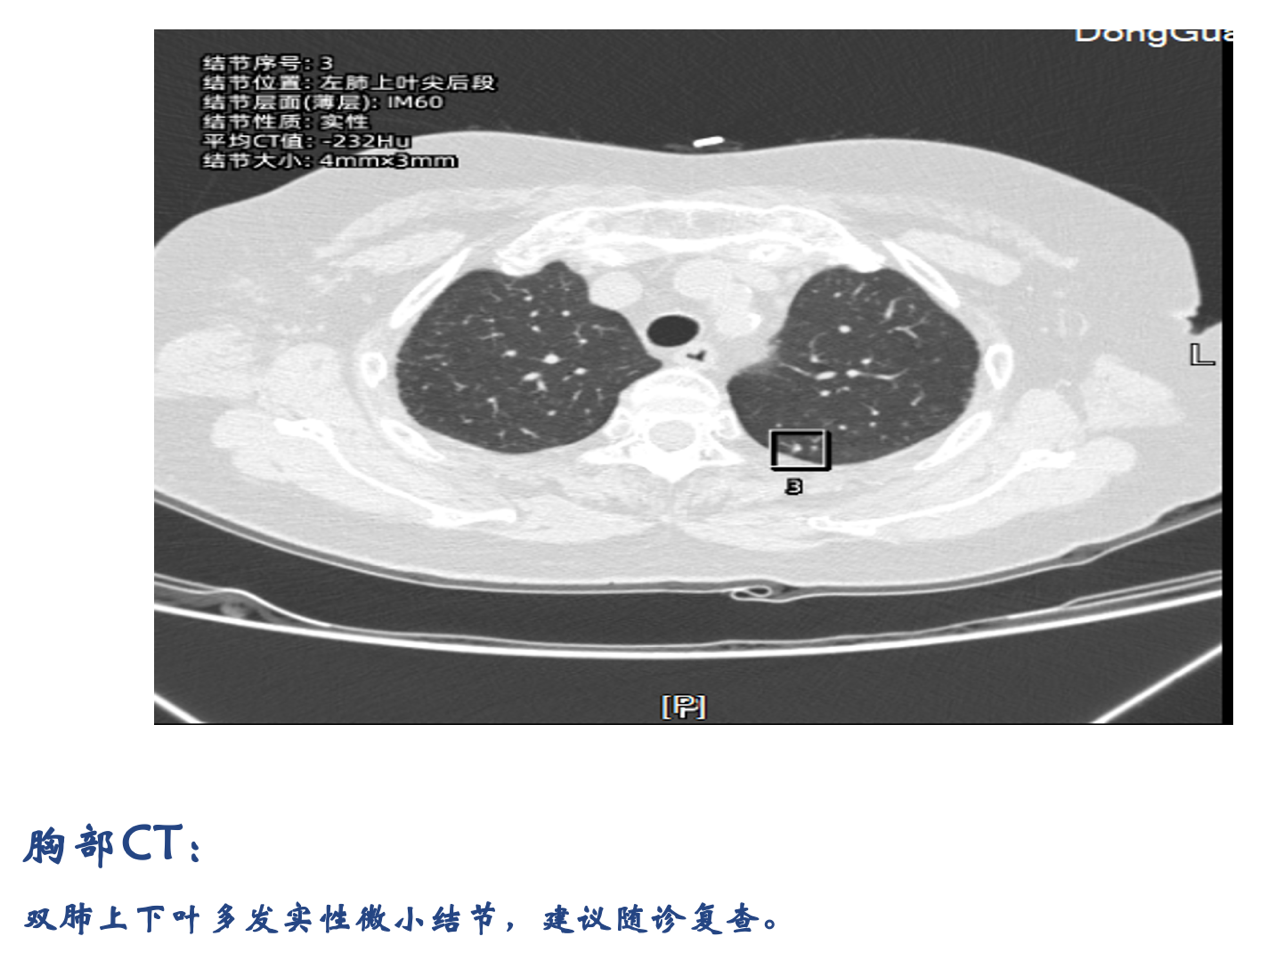

(2025-5-8)全身PET-CT检查:1.右侧乳腺外上象限软组织肿块,糖代谢增高,考虑乳腺癌,侵犯邻近右乳皮肤,与邻近右侧胸大肌可疑粘连,右乳头及乳晕、周围皮肤增厚,糖代谢增高,请结合临床。右侧腋窝多发高代谢淋巴结转移。2.双肺散在多发结节,糖代谢增高,考虑转移。

胸部CT检查结果:

此病例患者为72岁HR+/HER2-晚期老年乳腺癌女性患者,并发肺转移,接受瑞波西利联合来曲唑一线治疗后,影像学检查显示乳腺病灶PR、肺结节缩小,查体见肿瘤短期内缩小,患者病情维持稳定,且治疗过程中未见严重不良反应。目前仍在定期继续瑞波西利靶向治疗中。该病例的临床转归与既往研究的疗效数据高度契合,为瑞波西利广泛用于临床实践进一步提供了真实世界印证。